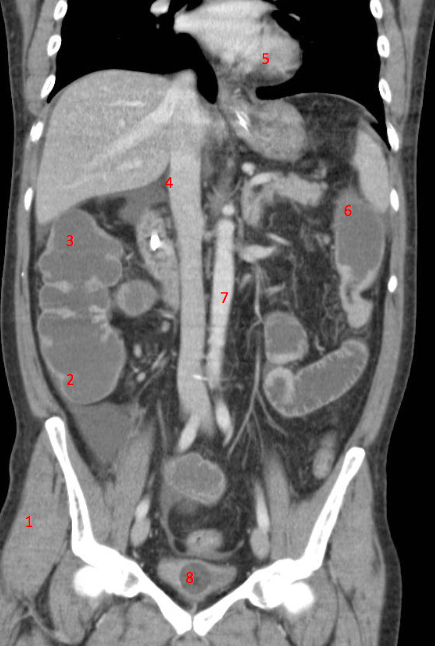

1

Number 3?

IVC

2

Number 1?

R Kidney

3

5

4

A

How well did you know this?

Not at all